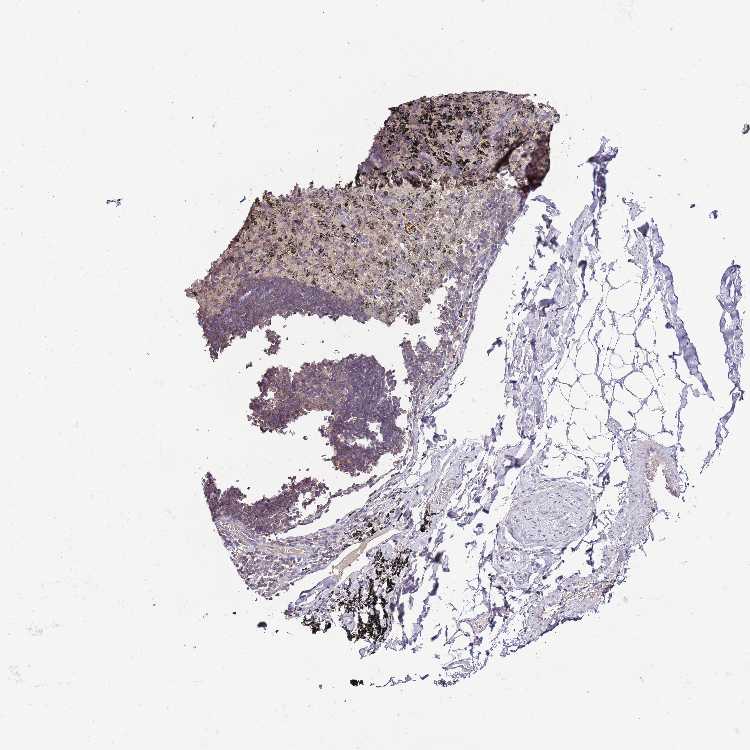

ADIPOSE TISSUE - Antibody stainingi

Antibody staining in the annotated cell types in the current human tissue is reported as not detected, low, medium, or high, based on conventional immunohistochemistry profiling in selected tissues. This score is based on the combination of the staining intensity and fraction of stained cells.

Each image is clickable and will lead to virtual microscopy that enables deeper exploration of all samples and also displays staining intensity scores, fraction scores and subcellular localization as well as patient and tissue information for each sample.

Antibody HPA048615

Adipocytes Not detected